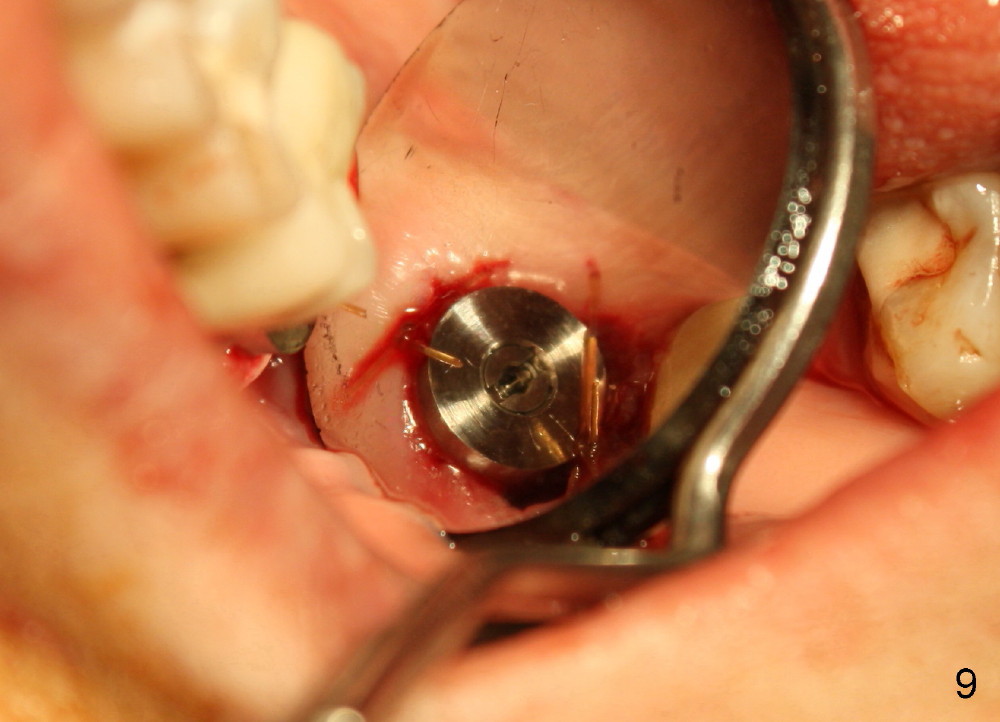

A 51-year-old lady has multiple restorations (Fig.1-3), e.g., amalgam (A in Fig.1) of the upper right 2nd molar as well as history of pulpotomy. The 1st molar has periapical radiolucency (* in Fig.1) and needs root canal therapy. The lower 3rd molar occludes (Fig.2 arrow) with the upper 2nd molar. The latter fractures subgingivally (Fig.3 <) and is extracted with a large MB root (Fig.4) and MB socket (Fig.5). The gingival one third of the palatal wall is defective, as indirectly indicated by granulation tissue palatally (Fig.5 <). So the osteotomy for the immediate implant will not be placed in the palatal socket. The septum is pointed coronally. The pointed portion of the septum is removed; initial osteotomy is formed by 1.5 mm pilot drill in the septum, followed by 2-5 mm osteotomes with the depth of 17 mm. The enlarging osteotomy is deviating buccally; drills are being used to move the osteoomy palatally without much success. When a 5 mm tap is inserted, it is stable and appears to be inside the maxillary sinus (Fig.6). In fact the osteotomy has bony walls around (Fig.7 <), including apical, when the tap is removed. Preop PA shows that the palatal root is apical to the sinus floor (Fig.1 between arrows).

Although the osteotomy appears mainly located in the buccal aspect of the socket apically, the implant (7x17 mm, Fig.8) is placed more or less in the middle of the socket (Fig.9). The trick is to lean the implant palatally while it is being inserted.